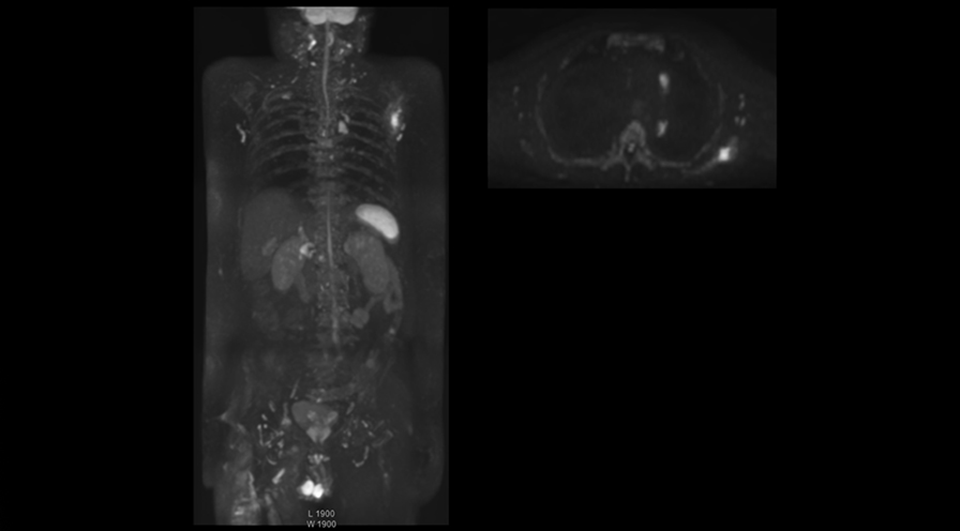

Recognizing the clinical utility of whole body MR imaging, radiologists at Kawasaki Saiwai Hospital (Kasawaki, Japan) began offering whole body diffusion weighted imaging (DWI) in 2009 for oncology patients. In 2012, the hospital installed a Philips scanner, the Ingenia 1.5T. The dStream digital architecture and highly linear gradients of Ingenia allowed them to switch to coronal – rather than axial – whole body DWI, and were key to developing a fast, high quality protocol that has led to increased referrals and decreased dependence on nuclear medicine imaging.

Radiologist Hiroshi Nobusawa, MD, PhD, explains that the coronal DWIBS protocol for whole body DWI is excellent for visualizing lesions in oncology patients. “About 90% of the DWIBS exams are done in this type of patients. The remainder of DWIBS exams are performed to gain information in cases of fevers of unknown origin,” he says.

“The DWIBS sequence’s value in oncology cases is due to the high contrast it creates between lesions and surrounding tissue. Whole body DWI is requested by physicians who need to clarify TNM staging or determine therapeutic strategies, oncologists in need of diagnosis or follow-up scans, surgeons who need to see the presence of distant lesions that are sometimes difficult to detect by CT before surgery, and urologists for the evaluation of bone lesions, and the effect of chemotherapy and radiotherapy.”

Coronal DWIBS is faster and improves image quality

“Switching to coronal DWIBS – rather than axial – further shortens scan time,” says Mr. Naka. “Important is that a dS SENSE factor of 5 shortens exam time while high image quality can be maintained, thanks to Ingenia’s dStream architecture.” He adds that the coronal orientation also avoids artifacts that are specific to combining axial images.

“When we use a coronal DWIBS acquisition, we can perform a full whole body examination, including other required sequences, within 30 minutes,” he says.

“This is considerably faster than the previously used exam with axial whole body DWI, which took more than 45 minutes,” he notes. “A shorter exam is more patient-friendly and allows us to also use it on patients in poor health who would have difficulty tolerating a long exam. Limiting the exam time is also helpful for scheduling, because it fits in a normal single exam timeslot.”